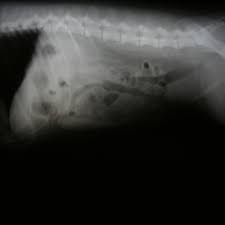

Pancreatitis In Dogs How To Spot It And Get It Treated

Pancreatitis In Dogs How To Spot It And Get It Treated from img.webmd.com

Pancreatitis In Dogs Symptoms Treatment Prevention

Pancreatitis In Dogs Symptoms Treatment Prevention from s3.amazonaws.com